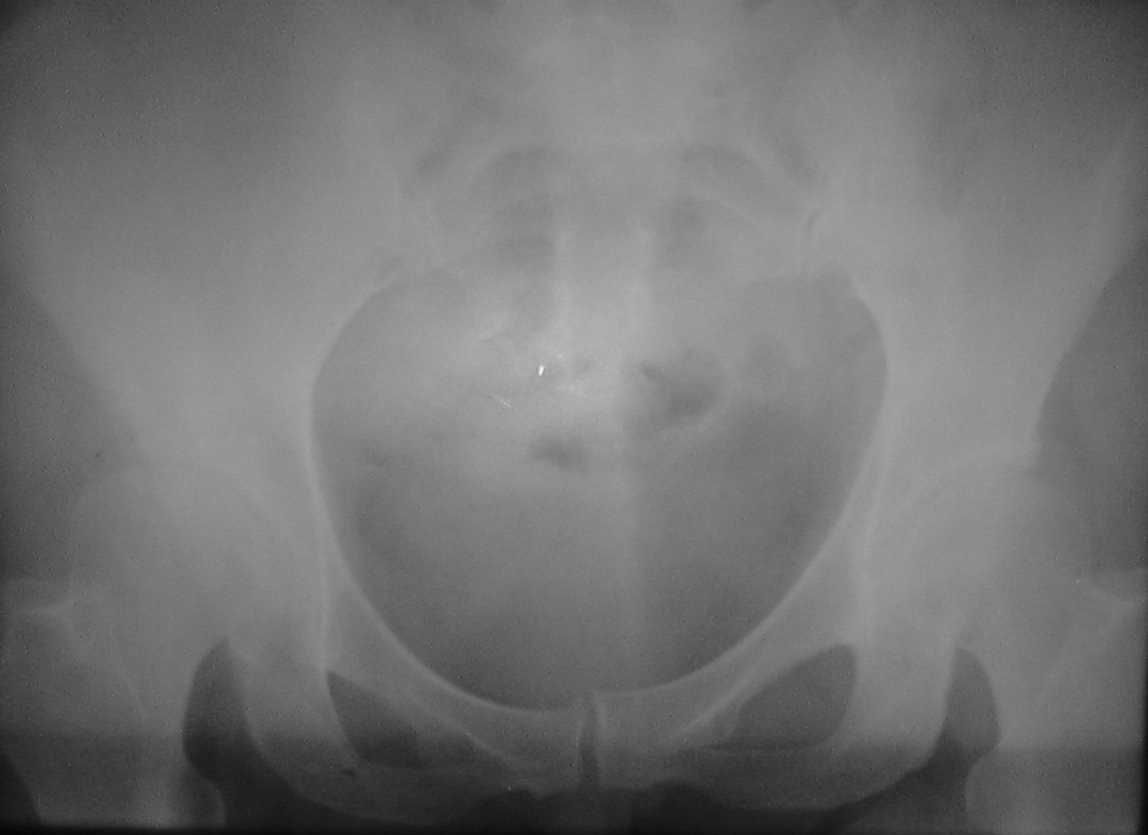

Re: нвообразование седалищной кости

послал ерохин александр 16 Январь 2007, 22:01

Спасибо всем,кто откликнулся, высылаю

обзорные снимки таза. Прошу извинения за качество снимков